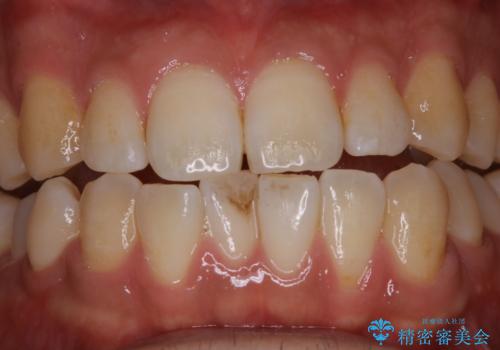

コーヒーの着色が前歯について目立つ

- コーヒーを毎日飲むので、どうしても着色がついてしまう。前歯の目立つ着色をきれいにとってほしいとのことでした。

PMTC60分コースを行いました。